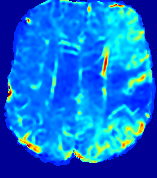

LesionRefer to captionRefer to captionRefer to captionRefer to captionRefer to captionRefer to caption𝐕rgbsubscript𝐕𝑟𝑔𝑏{\bf{V}}_{rgb}Refer to captionRefer to captionRefer to captionRefer to captionRefer to captionRefer to caption𝐕2subscriptnorm𝐕2{\|\bf{V}}\|_{2}Refer to captionRefer to captionRefer to captionRefer to captionRefer to captionRefer to captionRefer to caption3.53.53.52.82.82.82.12.12.11.41.41.40.70.70.70.00.00.0(mm/s)𝑚𝑚𝑠(mm/s)D𝐷DRefer to captionRefer to captionRefer to captionRefer to captionRefer to captionRefer to captionRefer to caption0.0200.0200.0200.0160.0160.0160.0120.0120.0120.0080.0080.0080.0040.0040.0040.0000.0000.000(mm2/s)𝑚superscript𝑚2𝑠(mm^{2}/s)Slice #1Slice #2Slice #3Slice #4Slice #5Slice #6

Figure 4: PIANO feature maps for another patient in the ISLES 2017 training set, where the lesion is located in the right hemisphere. Top row: segmented stroke lesion region (white) on different slices. The corresponding slices for the PIANO feature maps are shown in the following rows.

For a better insight into an estimated velocity field 𝐕𝐕{\bf{V}} and diffusion field 𝐃𝐃{\bf{D}}, we compute the following maps: (1) 𝐕rgbsubscript𝐕𝑟𝑔𝑏{\bf{V}}_{rgb}: Color-coded orientation map of 𝐕=(Vx,Vy,Vz)T𝐕superscriptsuperscript𝑉𝑥superscript𝑉𝑦superscript𝑉𝑧𝑇{\bf{V}}=(V^{x},V^{y},V^{z})^{T}, obtained by normalizing 𝐕𝐕{\bf{V}} to unit length and mapping its 3 components to red, green, blue respectively; (2) 𝐕2subscriptnorm𝐕2\|{\bf{V}}\|_{2}: 222 norm of 𝐕𝐕{\bf{V}}; (3) D𝐷D: scalar field in Eq. 5.

Fig. 3 and Fig. 4 show the PIANO feature maps estimated from two ISLES 2017 patients: all are highly consistent with the lesion in both cases. Details of the blood flow trajectories are revealed in 𝐕rgbsubscript𝐕𝑟𝑔𝑏{\bf{V}}_{rgb} by the ridged patterns and the sharp changes of colors in the unaffected (right) hemisphere, while the flat patterns appearing within the lesion provide little directional information about the velocity and indicate low velocity magnitudes. Velocity magnitudes are more directly visualized via 𝐕2subscriptnorm𝐕2\|{\bf{V}}\|_{2}, from which one can easily locate the lesion where 𝐕2subscriptnorm𝐕2\|{\bf{V}}\|_{2} is low. D𝐷D also indicates lower diffusion values in the lesion, though with less contrast potentially due to the fact that it captures the accumulated effect of CA diffusion at the voxel-level.